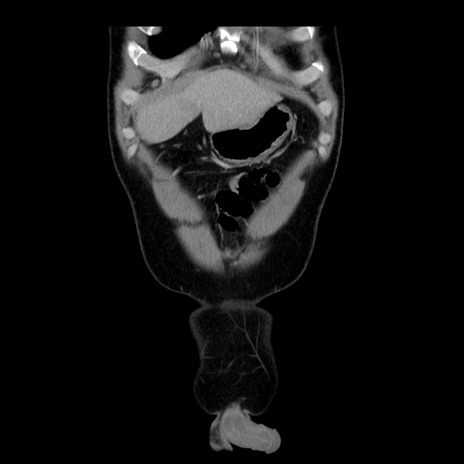

症例4(冠状断像)

【症例】30歳代男性

【主訴】腹痛、嘔吐

【現病歴】昨晩から突然の腹痛あり、その後嘔吐、軟便も出現。腹痛が改善しないため救急搬送となる。2日前にしめ鯖の食事歴あり。

【身体所見】意識清明、苦悶様、BP 135/90mmHg、BT 35.7℃、腹部:平坦、やや硬、心窩部〜臍部に自発痛、圧痛あり、筋性防御+、反跳痛-

【データ】WBC 8100、CRP 0.57